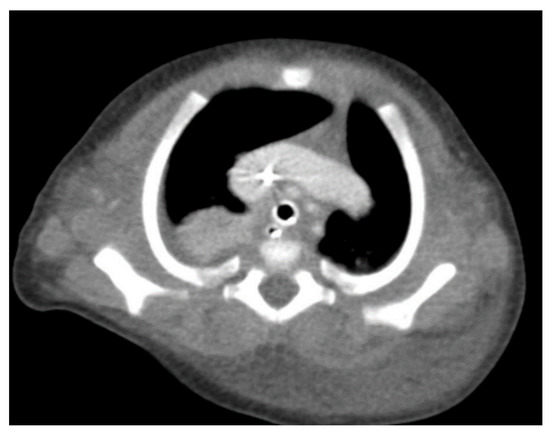

Through thoracic CT, we found SVC with a diameter of 15 mm (Figure 1), a venous collector with a 12 mm in diameter connected to the SVC and identified at the level of a plane passing through the middle of the left superior pulmonary lobe (Figure 2). The venous structure continues superiorly with the left brachiocephalic venous trunk, which was dilated up to 12 mm (Figure 3) and inferiorly with a left pulmonary vein. The pulmonary trunk appeared shorter, with a diameter of 6 mm, right pulmonary artery = 5.4 mm and left pulmonary artery = 5.6 mm (Figure 4 and Figure 5). We have identified traits of pulmonary consolidation (Figure 6).

Figure 6.

Pulmonary consolidation.